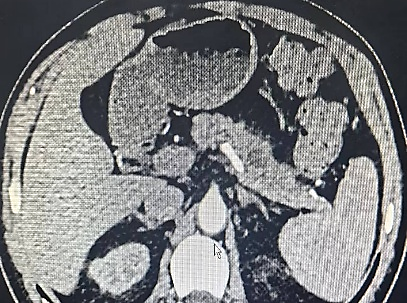

之后王志东教授团队又接诊一名60多岁的反复上腹隐痛来就诊的患者,外院上腹部彩超怀疑胰体尾占位。经腹部增强CT、肿瘤标志物检测及穿刺活检等检查,确诊为胰腺体部中分化腺癌。患者对术后生活质量有较高渴望,要求尽可能保留脾脏,如何在完整切除肿瘤的基础上保留脾脏,成为诊疗团队面临的核心挑战。

胰腺位于人体上腹部的深面,被胃肠、血管等脏器环绕,解剖结构较复杂,而胰体尾部癌因位置特殊,毗邻脾动静脉等重要血管,常常需要联合切除脾脏,而保留脾脏手术难度更是大幅提升。脾脏作为人体重要的免疫器官,承担着免疫防御、造血储血等关键功能,切除后增加术后感染、血小板升高致血栓、术后免疫力下降等并发症风险,影响患者近期、远期的生活质量。王志东教授团队术前反复研读影像学资料,精准评估肿瘤浸润范围、与脾动静脉的毗邻关系,逐一排查术中可能出现大出血、脾梗死、肿瘤残留等潜在风险,敲定个性化腹腔镜微创保脾手术方案,采用“保留脾动静脉的胰体尾切除术”(Kimura法)。